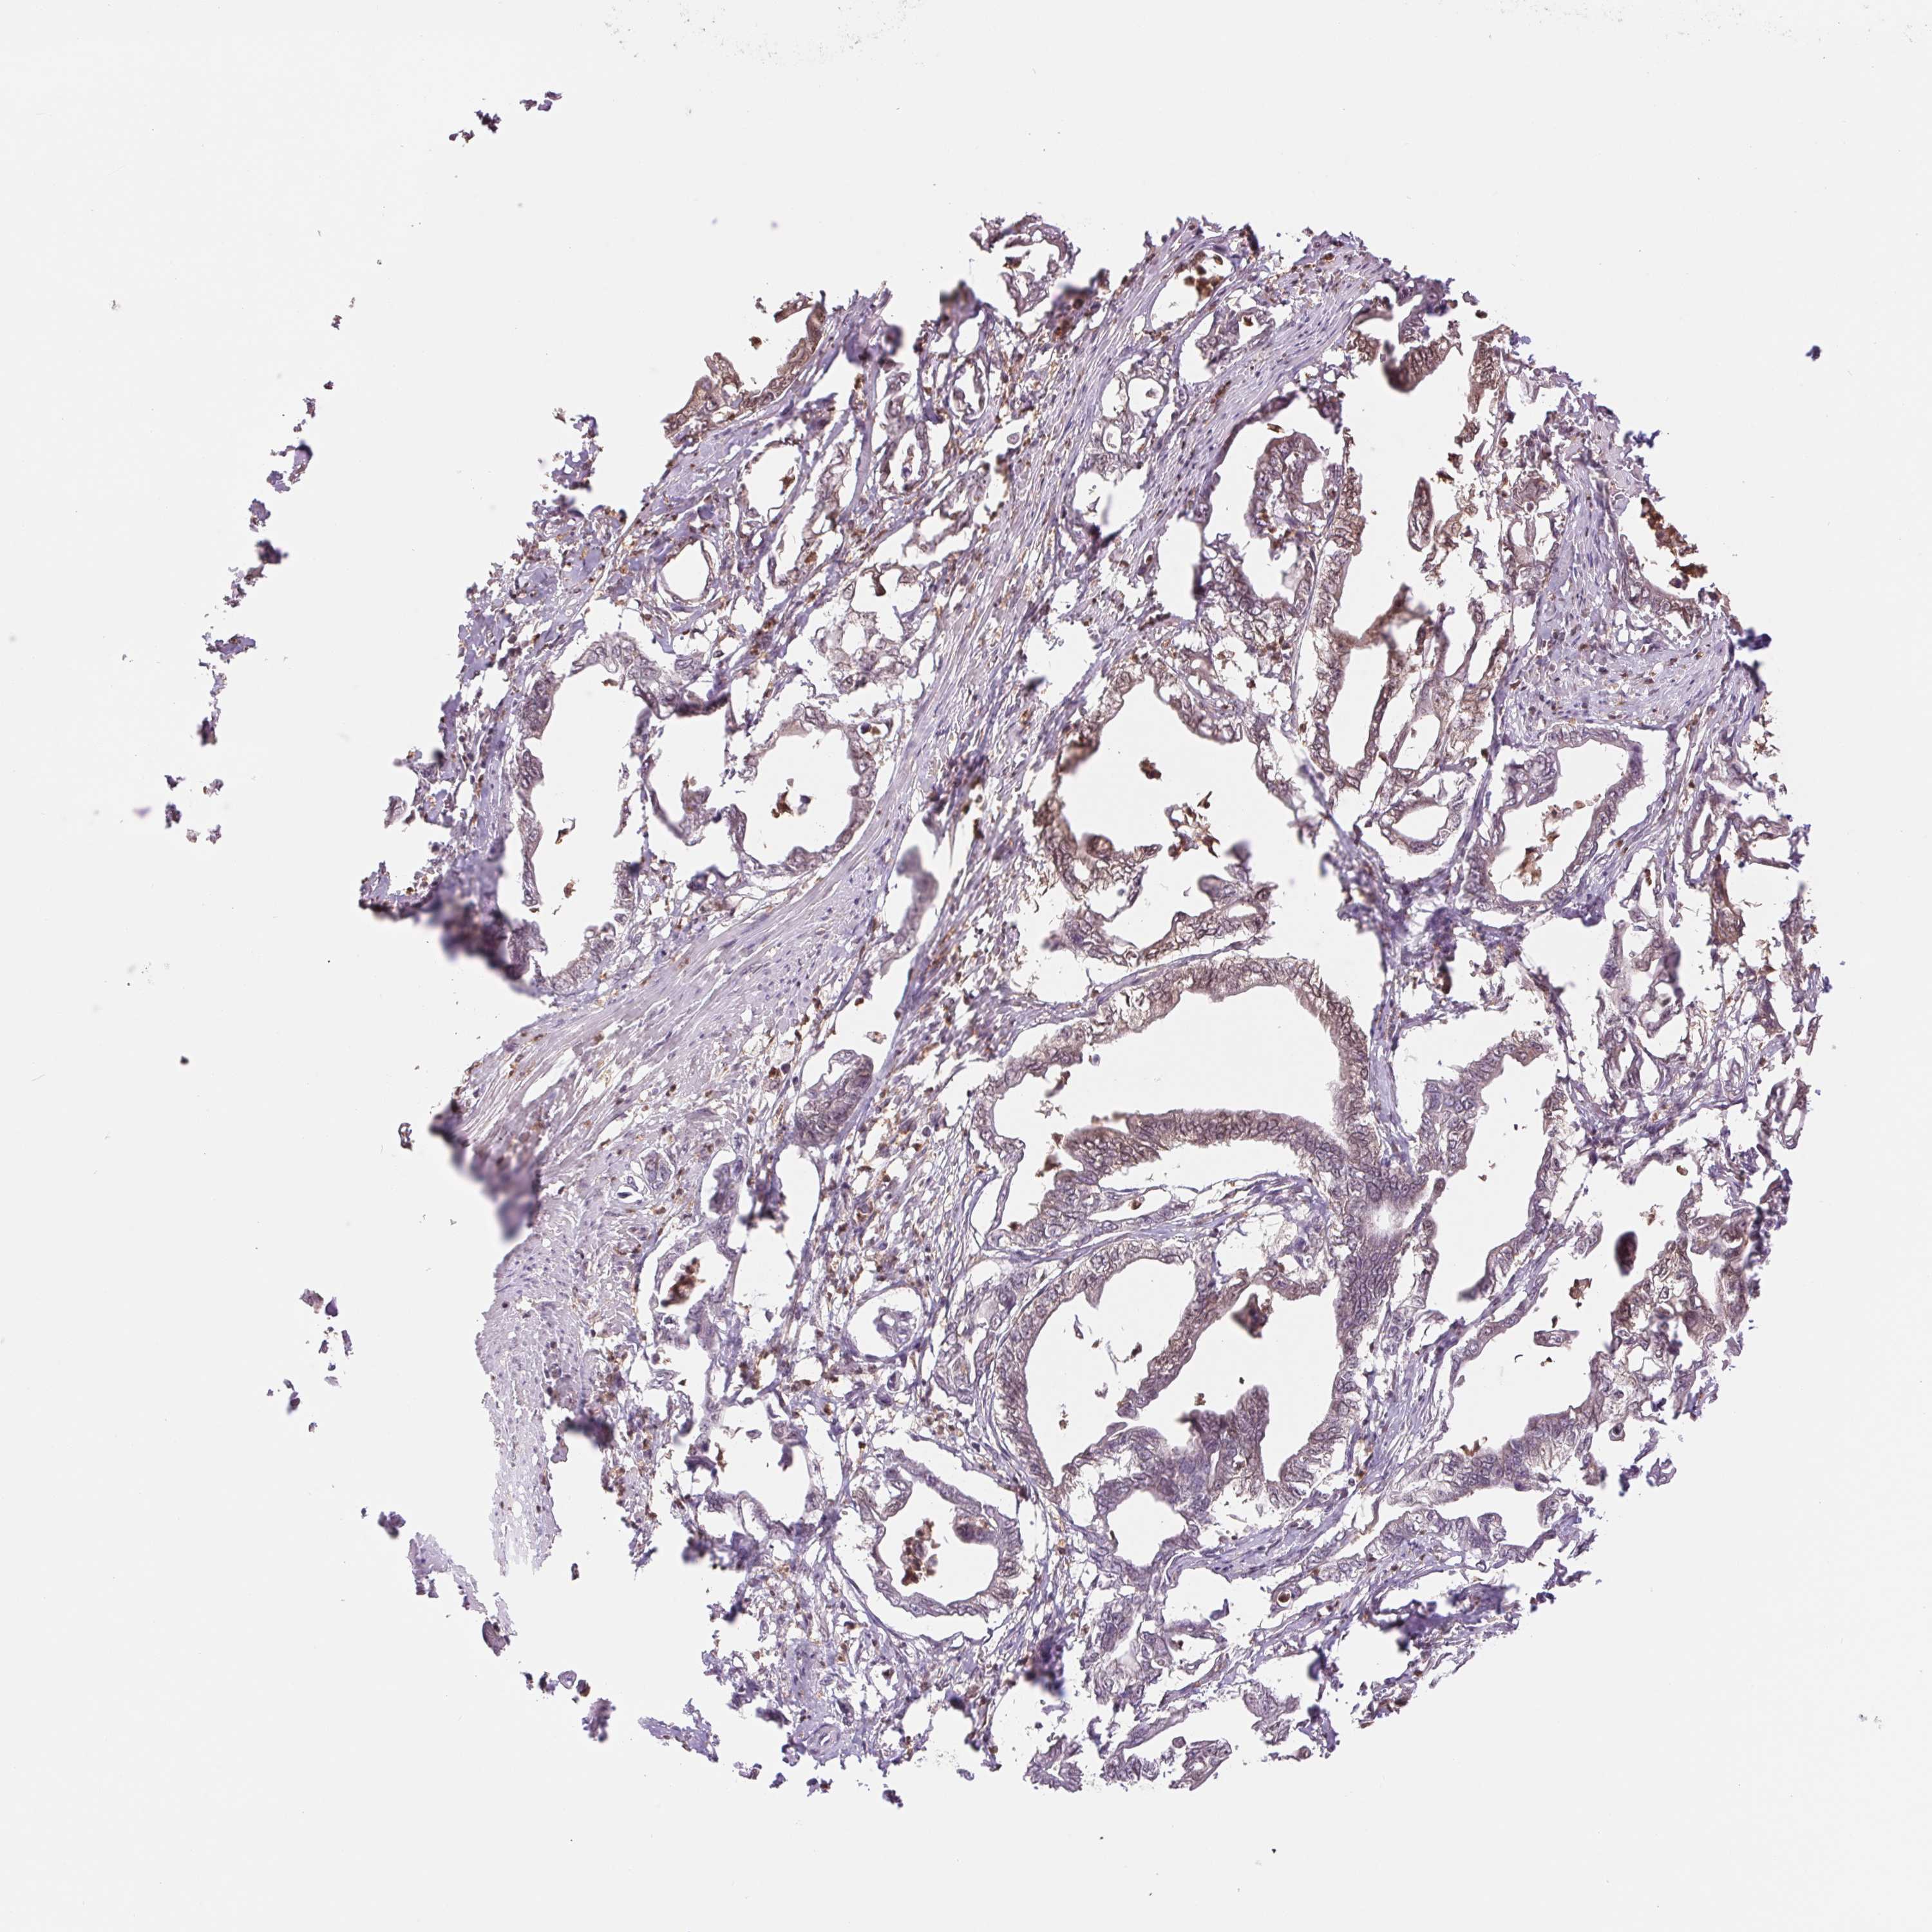

PANCREATIC CANCER - Protein expressioni

A mouse-over function shows sample information and annotation data. Click on an image to view it in a full screen mode. Samples can be filtered based on level of antibody staining by selecting one or several of the following categories: high, medium, low and not detected. The assay and annotation is described here.

Note that samples used for immunohistochemistry by the Human Protein Atlas do not correspond to samples in the TCGA dataset.

Antibody stainingi

Antibody staining in the annotated cell types in the current human tissue is reported as not detected, low, medium, or high, based on conventional immunohistochemistry profiling in selected tissues. This score is based on the combination of the staining intensity and fraction of stained cells.

Each image is clickable and will lead to virtual microscopy that enables deeper exploration of all samples and also displays staining intensity scores, fraction scores and subcellular localization as well as patient and tissue information for each sample.

Antibody HPA037830

Antibody HPA057540

Staining

High

Medium

Low

Not detected

Intensity

Strong

Moderate

Weak

Negative

Quantity

>75%

75%-25%

<25%

None

Location

Nuclear

Cytoplasmic/membranous

Cytoplasmic/membranous,nuclear

Adenocarcinoma, NOS